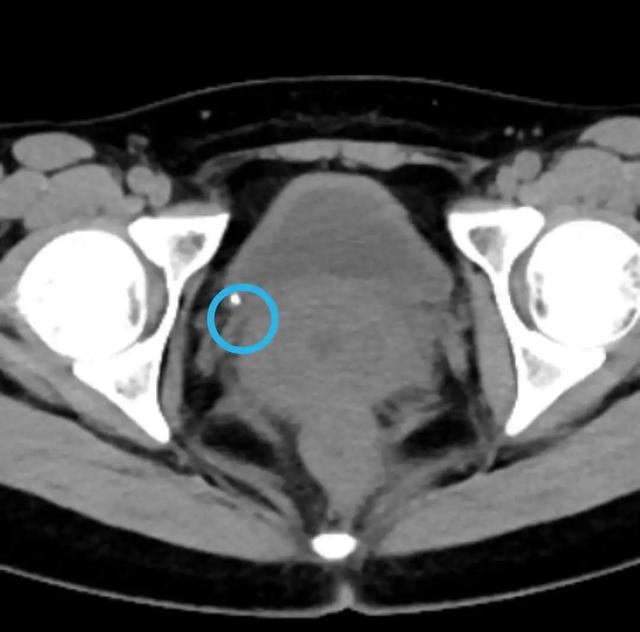

结石已经经过输尿管,滑落到了膀胱内,直径大约0.3公分。

但没想到,突然有一天剧痛无比,“忍不了了,忍不了了!”王先生这才赶紧上医院,腹部CT一检查,发现左侧输尿管中段多发结石,而且卡住后堵得上段的输尿管和肾盂扩张了,左肾周围已有液体渗出,右肾也有很多结石。